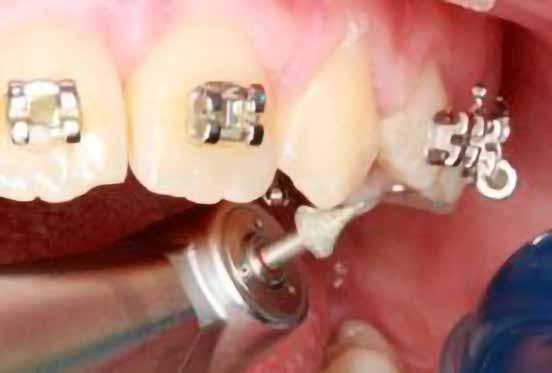

A szemfog elcsiszolásához piros gyémántfúró javasolt, finom szemcsézettséggel, 27-76 µm (okkluzálisan lekerekített – Rodentica, speciális hegyű 806314466514031, Komet 8833), gyorsítóval (max 160 000 fordulat/perc) megfelelő hűtés mellett, legalább 50 ml/perc. Ezt követi a felület kidolgozása és polírozása sárga gyémántcsiszolóval, extra finom szemcsézettséggel, 10-36 µm (Rodentica 806314466504031) és narancssárga Sof-Lex korongokkal (finom alumínium-oxid szemcsék 3-40 µm, extra finom, narancssárga-sárga, alumínium-oxid kristályok mérete 1,7 µm) könyökdarabban (25000 fordulat/perc) megfelelő hűtés mellett min. 50 ml/perc (2. a-d. ábra).

A szemfog megfelelő inklinációjának eléréséhez az oldalsó metsző helyén a palatinális felszínt is el kell csiszolni. Ennek a felületnek nem szabad interferenciát okoznia a harapásban, és lehetővé kell tennie a megfelelő metszőfog-vezetést [14]. A formázás előtt meg kell vizsgálni a szemfog vesztibulo-orális pozícióját. Lapos vesztibuláris felszínnel rendelkező szemfog esetén szükség lehet egy elsőrendű hajlításra a középső metsző és szemfog között (főleg, ha a szemfogon egy oldalsó metsző bracket van, melyben a beépített in-out érték magasabb) annak érdekében, hogy elérjük a megfelelő vesztibulo-orális pozíciót a fognyak szintjén, és elkerüljük a palatinális elcsiszolást (3. a-b ábra), [39].

A zománc elcsiszolásának mértékét az orális és incizális felszínen a harapás határozza meg, ennek vizsgálatához tükröt és artikulációs papírt használunk [36]. Ideálisan, teljes interkuszpidációban a frontális kontakt olyan enyhe, hogy az artikulációs papír kicsúszik, míg propulzióban, metsző fogvezetésnél a jelölésnek a palatinális felszín incizális harmadában kell lennie mind a középső metszőn, mind a szemfogon. A gyémánteszközök legalkalmasabb formája a palatinális elcsiszoláshoz a lándzsa és rögbi alakú (Komet 0640, piros finom lándzsa Rodentica 806314257514020 (max. 300 000 fordulat/perc), rögbi Rodentica 800314278514020 finom piros (27-76 µm) gyorsítóban. Ezt követően könyökdarabba fogott Sof-Lex korongokkal szükséges polírozni (4. a-b. ábra).